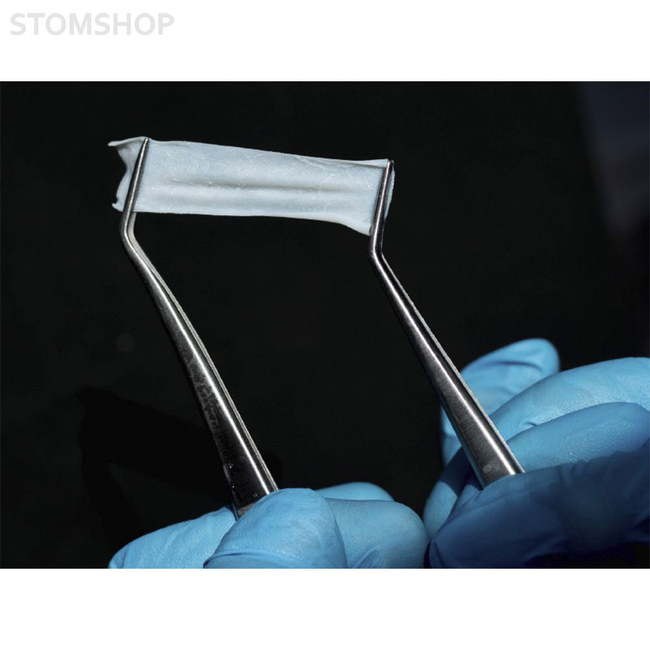

Еще более эластичная и гибкая. Адаптируется к любой форме дефекта, при этом прочная на разрыв. Легко фиксируется пинами и микровинтами. Мембрана cтабильно удерживает аугментат, обеспечивает оптимальные барьерные свойства даже при растяжении.

Состоит из коллагена I и III типа, имеет два слоя – серозный (гладкий) и фиброзный (ворсистый). При обнажении мембрана не инфицируется, ткани заживают вторичным натяжением. Предназначена для направленной костной регенерации (НКР) и направленной тканевой регенерации (НТР).